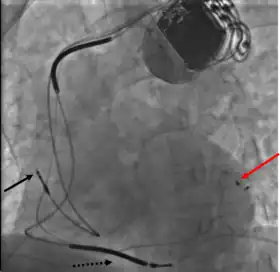

- Atrial lead at the right appendage

- Right ventricular lead at the apex

- Left ventricular lead through the coronary sinus.[7]

Right ventricular lead placement

A venipuncture is made, and a guide wire inserted into the vein, where it is guided, with use of real time X-ray imaging, through to the right ventricle. The guide wire is then used to assist in the placement of the electrode lead, which travels through the venous system into the right ventricle where the electrode is embedded.[1]

Left ventricular lead placement

This is generally performed subsequent to RV lead placement, with the RV lead providing a backup in case of accidental damage to the electric fibers of the heart, causing an asystolic event. As with the RV lead, a guide wire is first inserted, allowing for the insertion of a multi-delivery catheter. The catheter is subsequently maneuvered to the opening of the coronary sinus in the right atrium. From here a contrast media is injected, allowing the surgical team to obtain a coronary sinus phlebogram to direct the placement of the lead into the most suitable coronary vein.[1]

Once the phlebogram has been obtained, the multi-delivery catheter is used to guide in the lead, from the chosen vein of entry, into the right atrium, through the coronary sinus and into the relevant cardiac vein.[1]

Left ventricular lead placement is the most complicated and potentially hazardous element of the operation, due to the significant variability of coronary venous structure. Alterations in heart structure, fatty deposits, valves and natural variations all cause additional complications in the process of cannulation.[1]